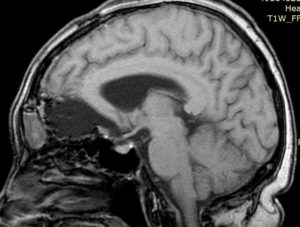

- Компьютерную томографию (КТ) — точность результата составляет 90%;

- Магнитно-резонансную томографию (МРТ) – с точностью 85%;

- МРТ – определяет наличие новообразования;

- КТ – определяет задействованность костной ткани и опухолевых кальцинатов;

- ПЭТ – определяет степень рецидива опухоли, т.е. распространения на другие части организма.

- МРТ – магнитно-резонансная томография является абсолютно безопасной, поэтому часто используется для проверки состояния пациента на ранних дооперационных стадиях и в период послеоперационного восстановления. МРТ помогает распознать рецидив заболевания, а также определить наличие опухоли при объеме всего в несколько миллиметров.

- Компьютерная томография – обследование проводится с контрастным усилением. КТ признаки указывают на наличие опухоли, а также помогают выявить природу новообразования, не прибегая к дополнительным диагностическим процедурам. Злокачественная опухоль имеет тенденцию накапливать контраст в своих тканях, что и становится очевидным на снимке КТ.